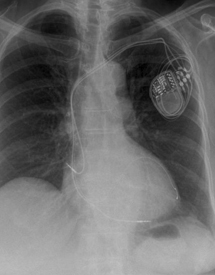

Pacemakers

Pacemakers are most commonly required for patients with a history of collapse or dizzy spells, when ECG monitoring shows that this is due to a slow heart rate. A pacemaker comprises of two main components, the "pacemaker box" which contains a battery and electrical circuit, and the pacing leads (usually one or two leads are required) which are passed along a blood vessel to the heart. The wires can sense when the heart beats normally and if the heart beats too slowly they can produce an electrical impulse to stimulate the heart. The pacemaker box is usually sited under the skin on the upper chest below the collar bone. The procedure is performed under local anaesthesia with sedation if needed. Patients usually need to stay one night in hospital.

A new type of pacemaker, known as a biventricular pacemaker or cardiac resynchronisation therapy is available for certain patients with heart failure. This usually requires 3 leads and improves the timing of the heart which usually leads to improved quality of life and has been shown to prolong life. These pacemakers are only suitable for certain individuals.

Another form of specialist pacemaker called an implantable cardiac defibrillator (ICD) can be implanted in patients who have survived a cardiac arrest or in patients who have had ventricular arrhythmias (fast heart rhythms from the bottom chambers of the heart). The lead detects abnormal rhythms and depending on how the device is programmed the ICD can try to rapidly pace the heart to stop the arrhythmia but if that is not effective it will then shock the heart to restore a normal heart rhythm. An ICD can be combined with a biventricular pacemaker (BiV-ICD) in selected patients with severe heart failure to improve symptoms and improve mortality.